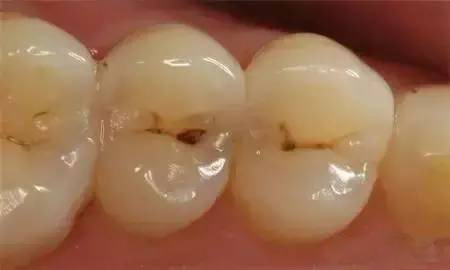

浅龋早期龋齿仅波及牙釉质,在釉质的表面出现大小不一的黄褐色斑点,一般无症状,常常不易被察觉,大多数患者在口腔检查时才发现。这一期的龋齿成为浅龋。中龋当龋坏进一步发展,波及牙本质浅层时,称为中龋。此时龋病进展快,易形成龋洞,呈黄褐色或深褐色。患者可有临床症状,常常表现为酸甜饮食或过冷过热饮食时牙齿感到酸痛,刺激去除后酸痛感立即消失;也有部分患者没有临床症状。

深龋若此时未得到有效控制,龋坏可继续向深层组织发展,当进展到牙本质深层时为深龋,牙齿出现很深的龋洞,食物可嵌入洞中。此时临床症状更为明显,刺激时产生的疼痛更剧烈,食物的压迫也会产生疼痛。 由于深龋离牙髓比较近,龋洞内的细菌和细菌所产生的毒素容易渗透到牙髓组织,可能引起急性牙髓炎,使患牙发生剧烈疼痛。